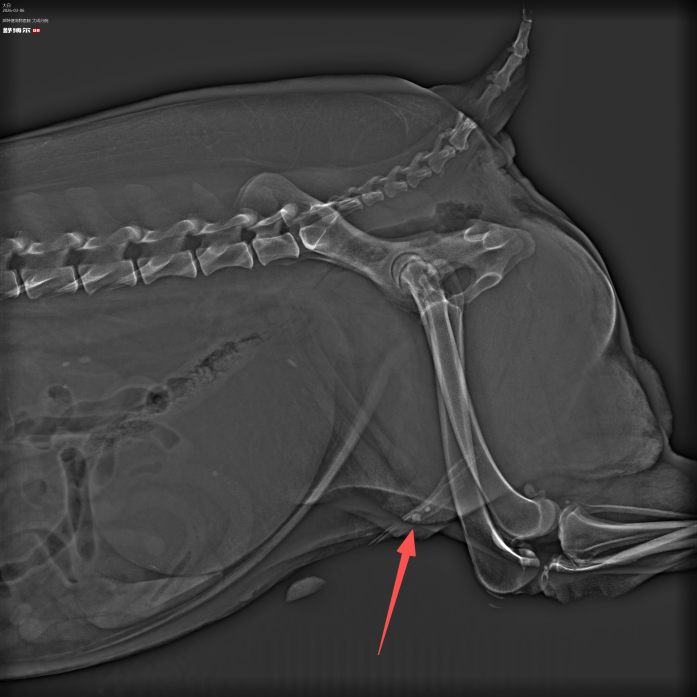

1.病例名称:铥激光+尿道内窥镜无创碎石术

2.患宠信息:10岁老龄犬

3.就诊原因:因尿道结石导致尿闭,无法正常排尿,精神沉郁,腹部胀满。

4.诊断难点:患宠年龄较大,麻醉风险高;结石位置深、分布广,同时累及尿道与膀胱,传统开刀手术创伤大、恢复慢。

5.治疗过程:采用铥激光碎石联合尿道内窥镜取石技术,在无需开刀、无需全身麻醉的情况下,精准定位结石,逐层粉碎并同步取出,全程无创完成尿道及膀胱内结石清除,最大限度降低手术风险。

6.康复情况:术后排尿通畅,精神状态良好,次日恢复正常饮食活动,无并发症,恢复周期显著缩短。